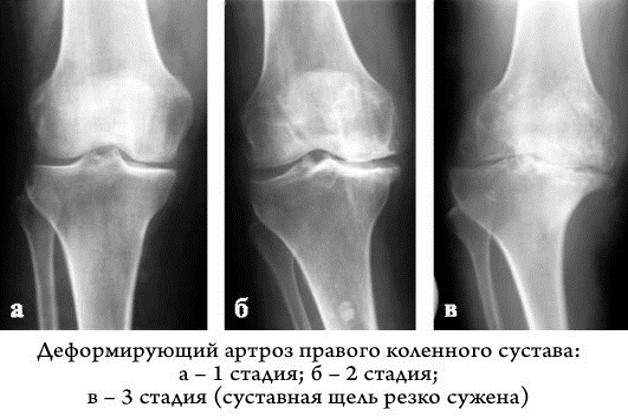

- На 1 степени хрящевая ткань теряет свою эластичность, ее структура становиться рыхлой. При движении маленькие частички слущиваются с поверхности и попадают в суставную область. После длительной ходьбы возникает дискомфорт и ощущение тяжести в колене. Сустав не деформирован.

- На 2 степени гонартроза происходит истончение хряща, кости начинают соприкасаться друг с другом, трение вызывает разрастание костных наростов (остеофитов). Болевые ощущения после длительной ходьбы ярко выражены, при движении можно услышать хруст, появляются «стартовые боли». Человек испытывает проблемы с разгибанием и сгибанием ноги.

- На 3 степени боль носит постоянный характер, движения ограничены. На рентгеновском снимке суставная щель практически не видна, по краям костных площадок располагаются массивные остеофиты. При движении шипы откалываются и попадая в суставной просвет блокируют колено, вызывая мучительные боли. Движения ограничены или отсутствуют. Происходит вальгусная или варусная деформация.

Существует три степени деформирующего артроза колена. Первая степень характеризуется легкими болями и минимальными изменениями на рентгенограмме. Вторая степень проявляется более выраженной болью и умеренными изменениями, такими как сужение суставной щели. Третья степень — это тяжелая форма, при которой наблюдаются значительные изменения в суставе, сильная боль и ограничение подвижности.